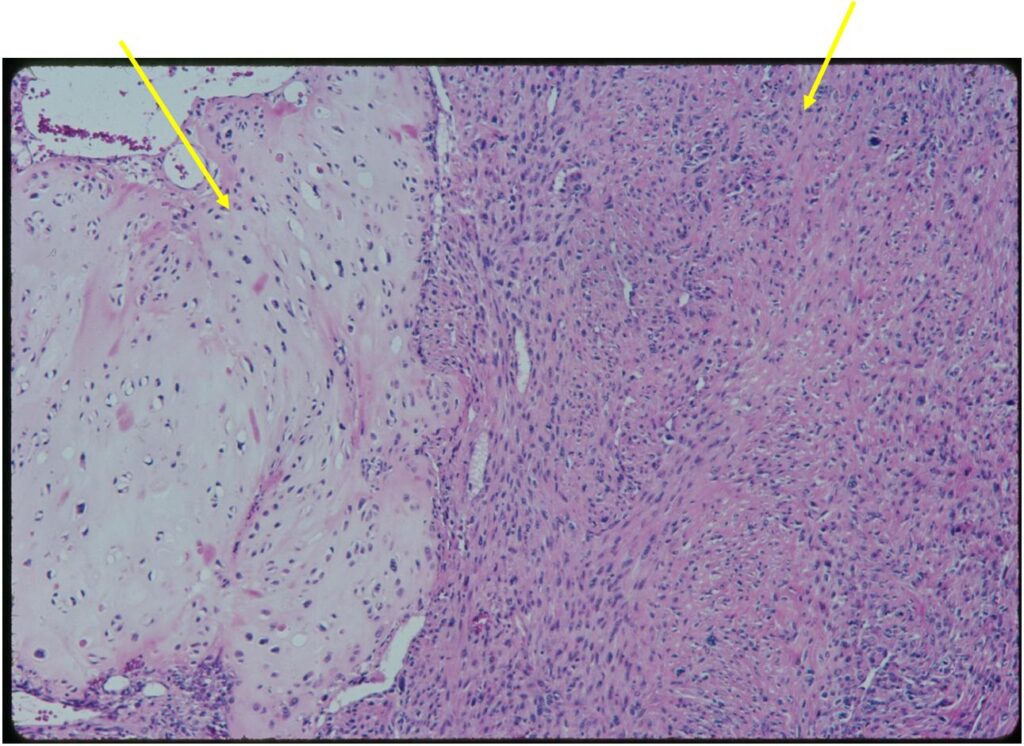

Junction of cartilaginous and noncartilaginous components is sharp and distinct. There are no dedifferentiated areas admixed in the middle of the cartilaginous areas

(Right Arrow) Spindle Cell Component

(Top Arrow) High Grade Dedifferentiated Spindle Cell Sarcoma Component

(Left Arrow) Low Grade Cartilage Component

(Right Arrow) Low Grade Cartilage Component

- Chondrosarcoma component is often grade I (Low Grade Hyaline Type Cartilage)

- Dedifferentiated component